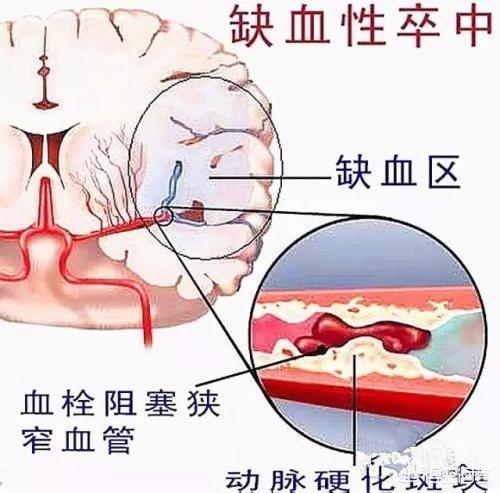

De nombreux ruraux ne reconnaissent pas l'infarctus cérébral. Qu'est-ce que l'infarctus cérébral ? L'infarctus cérébral est une maladie dans laquelle divers emboles sanguins (par exemple, un thrombus fixé à la paroi du cœur, une plaque d'athérosclérose, de la graisse, des cellules tumorales, du fibro-cartilage ou de l'air, etc.) pénètrent dans les artères cérébrales avec le flux sanguin et obstruent les vaisseaux sanguins, provoquant une nécrose ischémique des tissus cérébraux dans la zone desservie par les artères.

Pour simplifier, il s'agit de la nécrose des cellules cérébrales qui se produit lorsque les vaisseaux sanguins du cerveau sont bloqués, provoquant une ischémie cérébrale.

- Thrombose cérébrale :(1) Formation de caillots sanguins en raison de l'augmentation de la viscosité du sang. (2) Obstruction de la circulation sanguine due à l'accumulation de graisse dans les artères du cerveau, qui forme une plaque et aggrave le rétrécissement des vaisseaux sanguins dans le cerveau.

- embolie cérébraleLes obstructions provenant d'autres parties du corps que le cerveau, telles que les caillots sanguins, la graisse, les bulles d'air, etc., pénètrent dans les vaisseaux sanguins cérébraux via le système circulatoire et provoquent une perturbation localisée de la circulation sanguine cérébrale.